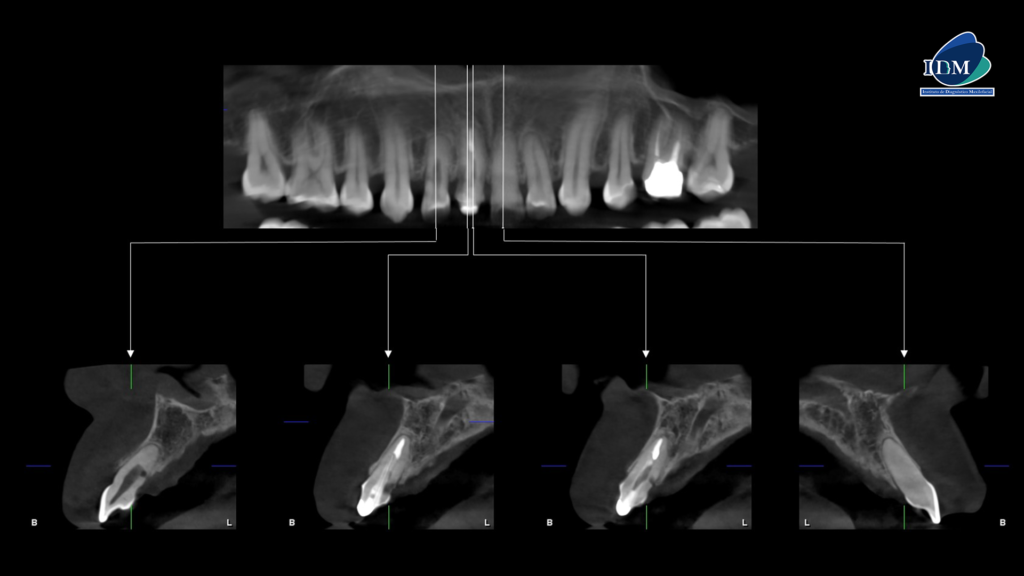

A la evaluación de la tomografía volumétrica (CBCT) en los cortes axiales (Figura 2) y transaxiales (Figura 3), se aprecia en pieza 12 obliteración del tercio apical e imagen hipodensa en pared radicular distal y palatino en tercio cervical y medio; pieza 11 tallado coronario, espigo, obturación de conducto, imagen hipodensa en pared radicular distal y palatino en tercio cervical y medio; pieza 21 obliteración de conducto radicular.

CORTES TRANSAXIALES